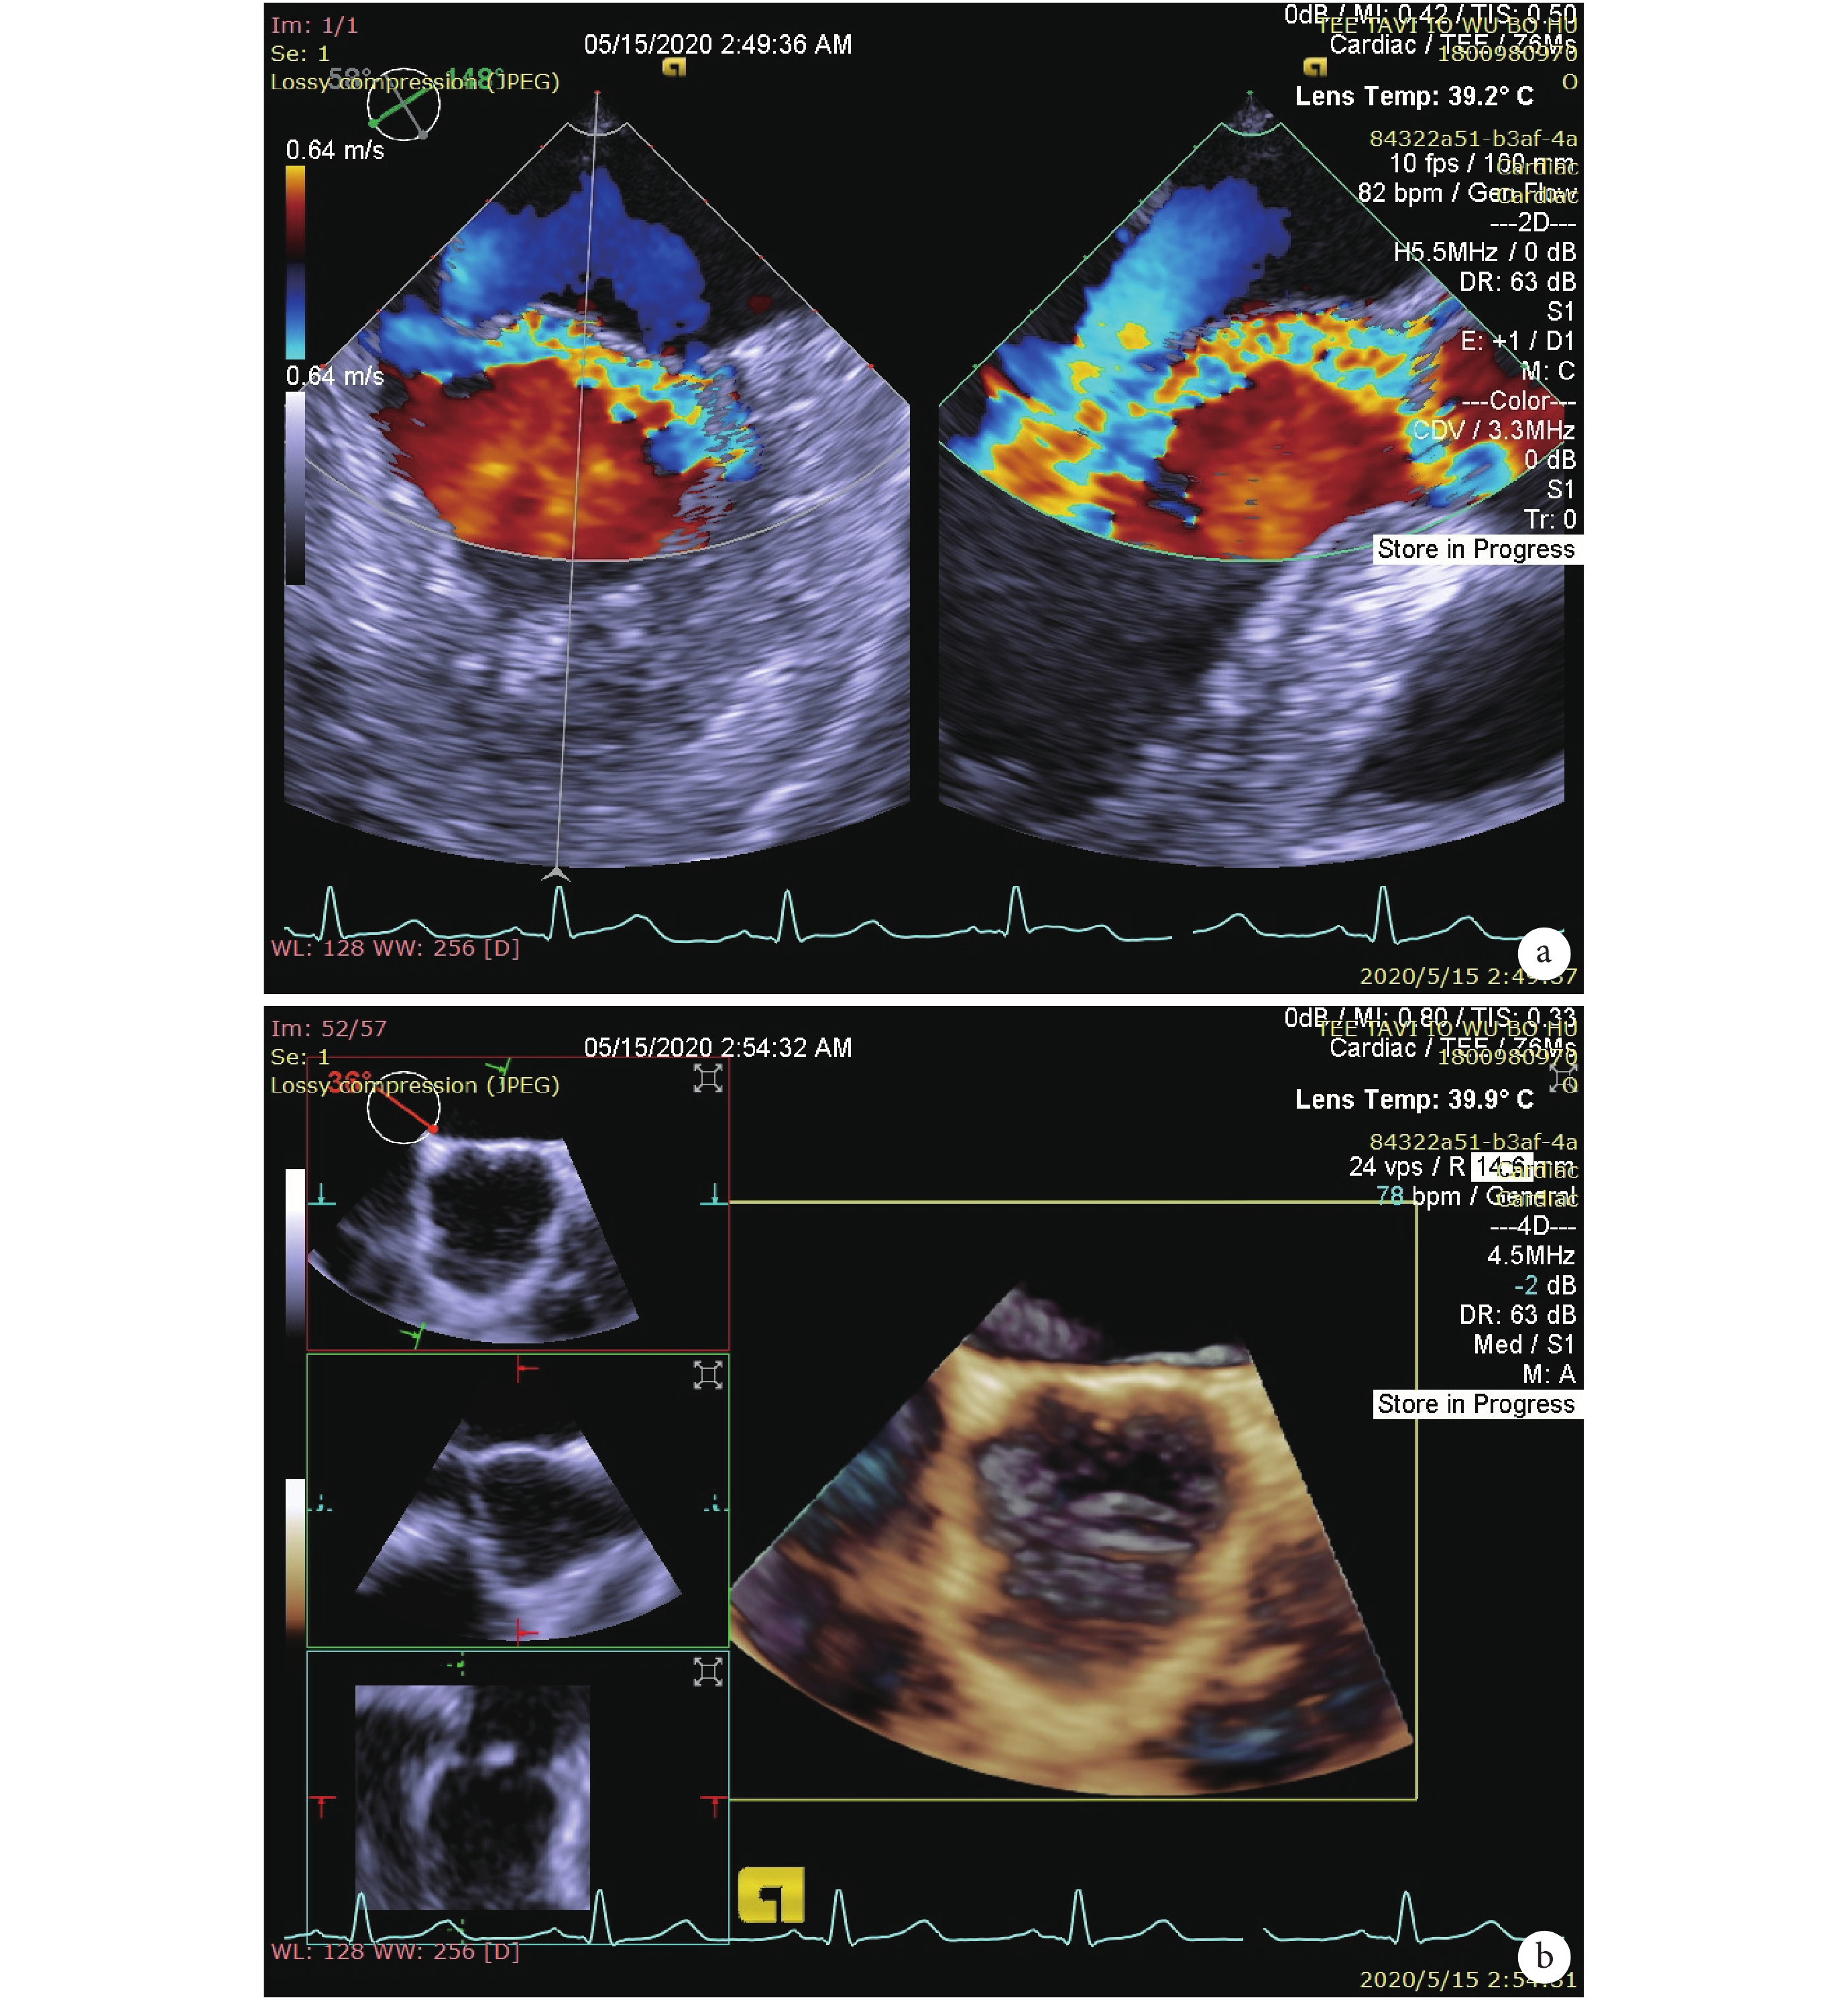

1 例術中瓣膜移位至主動脈弓部,轉行 SAVR,術中將移位 J-valve 瓣膜取出,置換金屬機械瓣,術后患者恢復良好,術后 10 d 出院,推測瓣膜移位原因是瓣膜改加補片后,瓣環直徑仍偏小,造成釋放后位置不穩定而移位;余 9 例植入 29#J-valve 瓣膜,所有患者無需植入第 2 枚支架瓣膜。術后心功能分級(NYHA)Ⅱ級 6 例,Ⅲ級 4 例,LVEF(44.70%±8.78 % vs. 39.80%±8.48%,P<0.05),主動脈瓣反流[(1.75±0.72)mL vs.(16.51±8.71)mL,P<0.05],術后即刻存在少量或微量瓣周漏[(1.20±1.16)mL]。手術過程無體外膜肺氧合支持、快速起搏或植入前球囊擴張成形。術中無Ⅲ度房室傳導阻滯、冠狀動脈開口阻塞、瓣環破裂或腦血管意外發生(表 2、圖 6),術后利用患者 CT 復查數據進行重建并結合 3D 打印技術進行術后影像學評價(圖 7)。

a:二維超聲顯示瓣膜位置良好;b:支架瓣膜位置良好,無反流